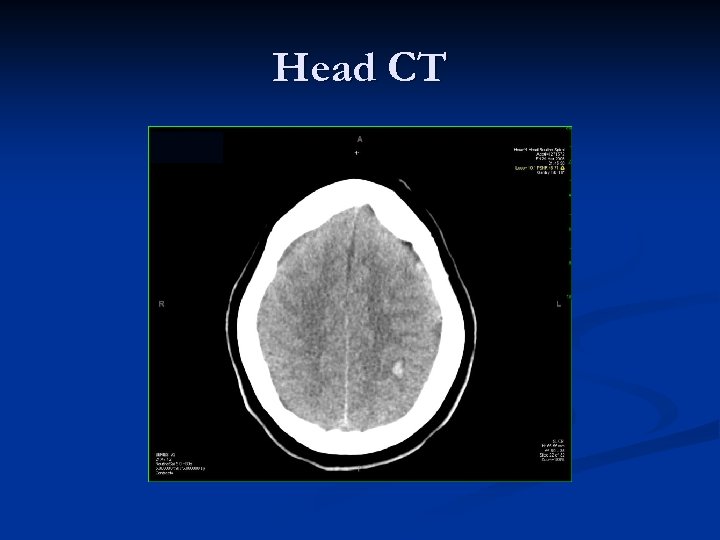

Head CT

Head CT IMPRESSION: 1. SMALL (10. 7 x 8. 5 mm) PARENCHYMAL HEMORRHAGE AT THE LEFT PARIETAL GREY-WHITE MATTER JUNCTION. 2. SUGGESTION OF VERY MILD EDEMA IN LEFT HEMISPHERE WITH 5 MM MIDLINESHIFT TOWARDS THE RIGHT. n